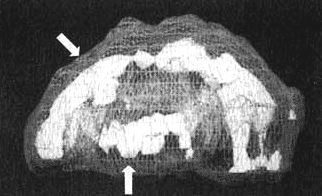

Трехмерное изображение - активный мозг, вид сбоку. Обратите внимание на выраженное повышение активности в поясной системе и в левой височной доле (см. стрелки).

Трехмерное изображение - активный мозг, вид сбоку